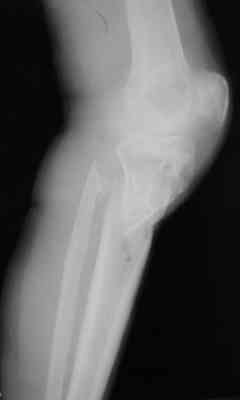

Опять мало информации. Это снимки от августа 2006. А что сейчас в двух проекциях? Что растет в посевах? Насколько заинтересован коленный сустав: движения, синовит? Чего хочет больной?

Р-граммы за март и апрель

Р-граммы и фото за 4.05.2007 - 7-е сутки после операции.

Ход операции - линейным разрезом по передней поверхности голени обнажена зона ложного сустава большеберцовой кости. От кости отсепарованы медиально м/ткани. Из зоны ложного сустава убраны рубцовые ткани, мобилизован дистальный отломок. По передней поверхности удалены два осколка, связанных грануляциями. Произведено удаление грануляционной ткани из проксимального отломка (на вид сине-серого цвета), "чистого" гноя не было. Затем произведено наложение аппарата и репозиция отломков. По передне-медиальной поверхности образовался дефект до 4х2х2 см + полость в проксимальном отломке. Удаленные осколки очищены от грануляций, уложены в место дефекта, зажаты между отломками. После иссечения раны по передней поверхности, находящейся рядом с операционной раной, последняя ушита с большим натяжением.

Перелом мыщелка сросся. Проксимальный отломок очень порозный.